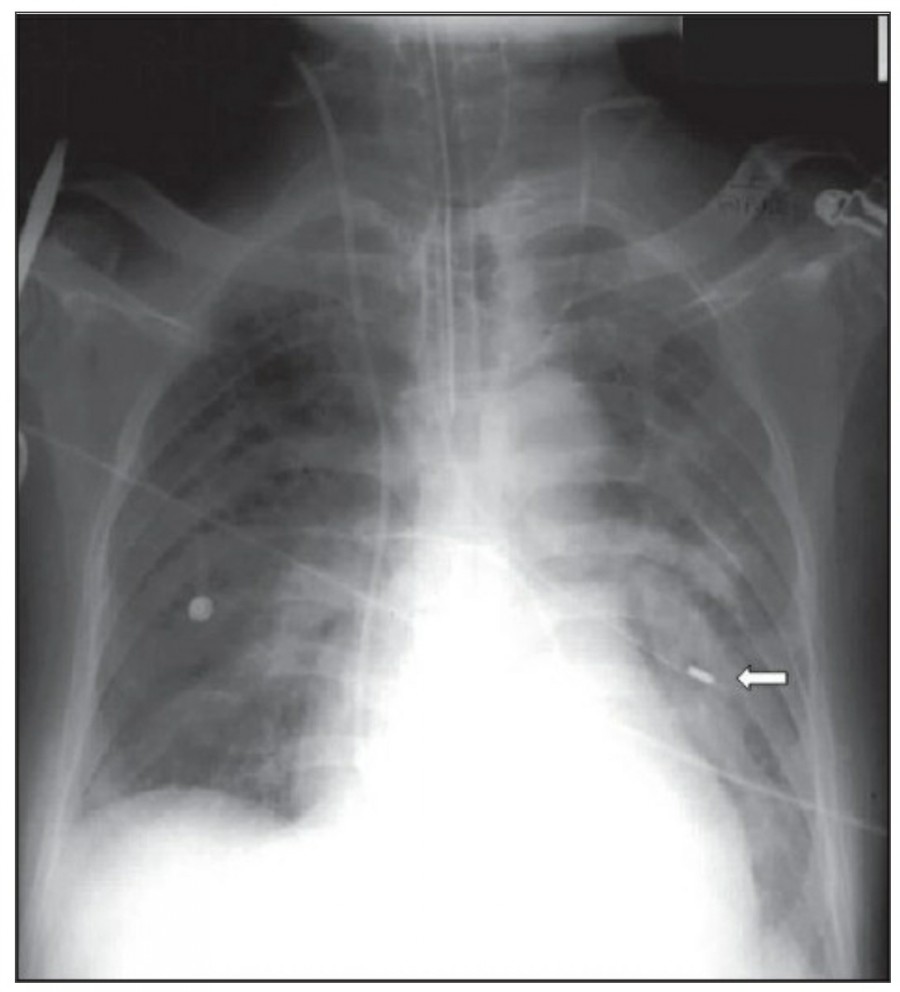

The feeding tube

Nasogastric tube 삽입은 의식이 없는 환자나 bronchial tree로 들어갈 위험이 높을 때는 chest X ray를 확인해야 한다. 또한 small-bore feeding tube를 삽입하거나 esophagectomy 환자에서 tube를 넣을 때도 chest X ray 확인이 필요하다. NG tube의 lower tip은 보통 abdominal radiograph로서 확인할 수 있다.